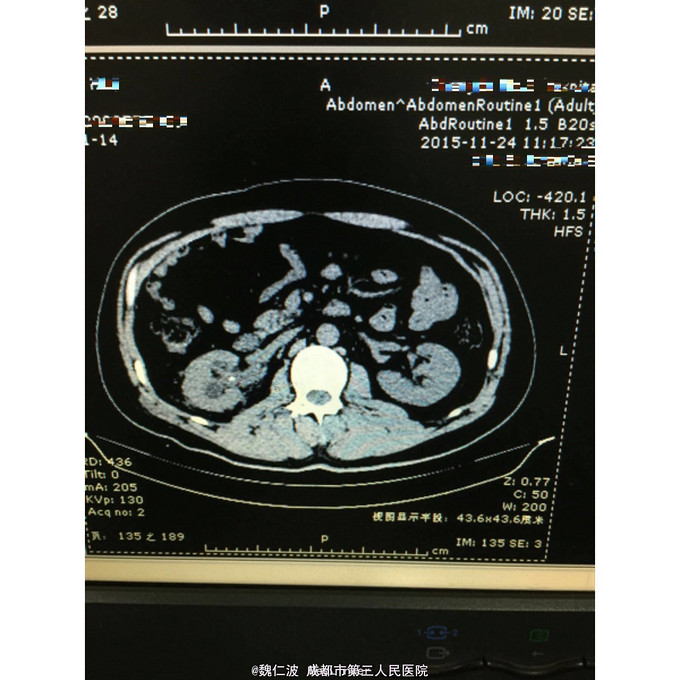

右侧输尿管结石碎石术后3月,发现右侧输尿管上段闭锁4天 3月前因右侧输尿管上端结石行输尿管软镜钬激光碎石,术后恢复可,但拍石稍差,1月后取支架管,术后2月复查右侧肾积水1厘米,3月复查积水5Cm,外院行右肾穿刺造瘘术,发现右侧输尿管上端闭锁,遂来我院。

右侧输尿管上端闭锁,右肾结石,右侧输尿管上端结石 经抗感染治疗后,行开放狭窄段切除,输尿管吻合术,安置F8输尿管支架管。

输尿管结石常合并息肉形成,结石处理后往往伴随着狭窄问题,会给临床医生带来不小麻烦。术前后均需充分告知,并定期随访。 但有无好的处理方式,可以减少术后狭窄的发生呢?谢谢大家不吝赐教!